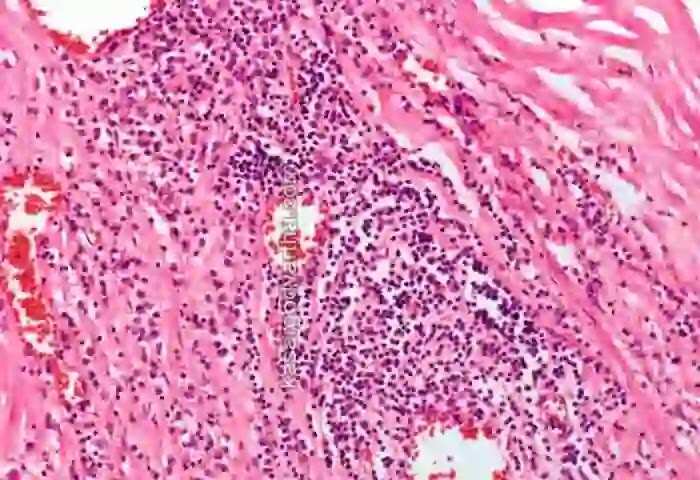

അമേരിക്കയിൽ, കഴിഞ്ഞ കുറച്ച് ദിവസങ്ങളിൽ, നേരത്തേതുമായി താരതമ്യം ചെയ്യുമ്പോൾ രോഗബാധിതരുടെ എണ്ണം 90 ശതമാനം വരെ വർധിച്ചതായി അധികൃതർ വ്യക്തമാക്കി. ട്രെപോണെമാ പല്ലിഡം (Treponema palli-dum) എന്ന ബാക്ടീരിയ മൂലമുണ്ടാകുന്ന ലൈംഗികരോഗമാണ് സിഫിലിസ്. അടുത്ത സമ്പര്ക്കത്തിലൂടെ ഒരു വ്യക്തിയില്നിന്ന് മറ്റൊരു വ്യക്തിയിലേക്ക് സിഫിലിസ് പകരുന്നു. ലൈംഗിക അവയവങ്ങളില് കൂടിയോ മലാശയത്തില് കൂടിയോ ആണ് ബാക്ടീരിയ പ്രധാനമായും പകരുക. ശാരീരിക ബന്ധങ്ങൾ വഴിയും രോഗബാധിതനായ വ്യക്തിയുടെ ഏതെങ്കിലും മുറിവുമായി സമ്പർക്കം പുലർത്തുന്നതിലൂടെയും ഈ ബാക്ടീരിയകൾ പകരാം. രോഗമുള്ള ഗര്ഭിണിയിലൂടെ ഗര്ഭസ്ഥശിശുവിനും ഈ രോഗം പകരാം.